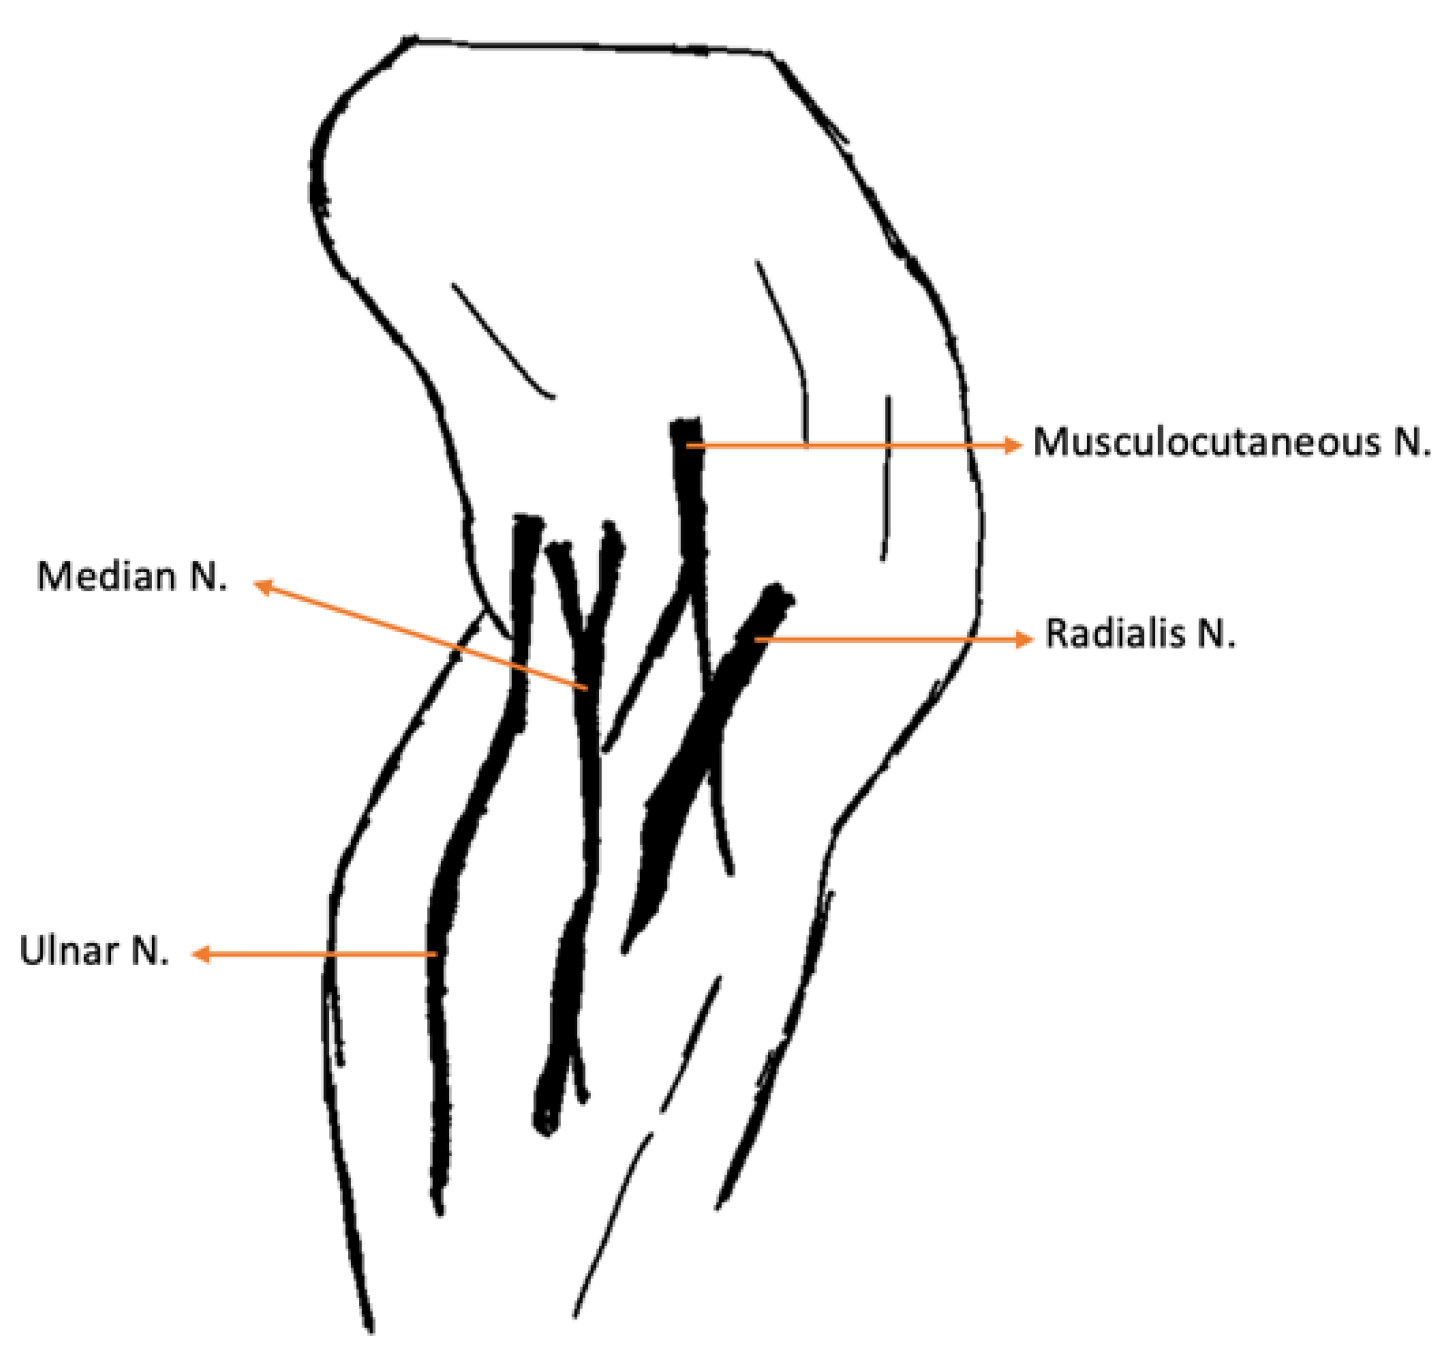

| Nerve | Origin | Innervated muscles |

|---|---|---|

| Radial | C6, C7, C8, T1, T2 | Extensor carpi ulnaris; Triceps brachialis; Extensor carpiradialis; Lateral and common digital extensor |

| Ulnar | C8, T1, T2 | Deep digital flexor; Flexor carpi ulnaris |

| Median | C7, C8, T1 | Superficial digital flexor; flexor carpi radialis |

| Lateral thoracic | C8, T1 | Cutaneous trunci |